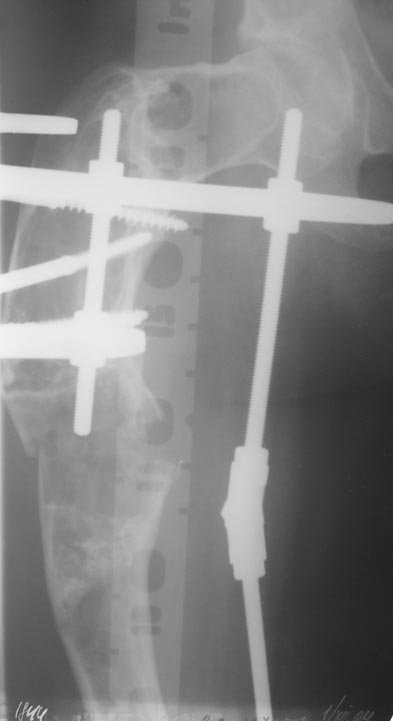

Женщина 28 лет, Больна с 12 летнего возраста, Когда после адекватной травмы получила перелом бедра. На рентгенограммах выявлено какое-то (рентгенограмм и документов нет) изменение бедренной кости, была оперирована, имеется гистологическое заключение - фиброзная дисплазия.дСформировалась деформация бедра. На сегодня - Укорочение 7см. Грубая деформация бедра по типу "пастушьей палки", последний патологический перелом в январе 2004г., консолидировавшийся при консервативном лечении. Имеются грубые изменения и в надвертлужном массиве.-- С уважением, Leonid

Возможна аппаратная коррекция оси с формированием клиновидного регенерата, которая решила бы и проблему укорочения (что, впрочем, нужно уточнить по схеме, сделанной по рентгенограмме с хорошим захватом смежных суставов - схемка по присланному снимку в приложении). По окончании коррекции - блокируемый стержень, который и сократит время пребывания в аппарате, и вообще возврата к нормальной жизни, а также будет мерой профилактики патологических переломов.

Уважаемые коллеги! Большое спасибо за живой отклик и предложения по тактике лечения. Больной произведен первый этап - стержневой аппарат издвух баз, кортикотомия, остеоклазия и начата коррекция в аппарате. Почти исправлен угол, не сегодня укорочение 2см. Когда завершим коррекция, представлю рентгенограммы.

Leonid Pollyak 02 Январь 2005, 22:42

Хотелось бы показать, что получилось в результате.

Операция выполнялась с помощью А.Н.Челнокова. Очень понравилась технология выполнения блокируемого остеосинтеза с использованием спицевого дистрактора, модифицированный гвоздь с латерализованным проксимальным отделом и возможностью многовинтовой фиксации проксимального и дистального участков бедра.